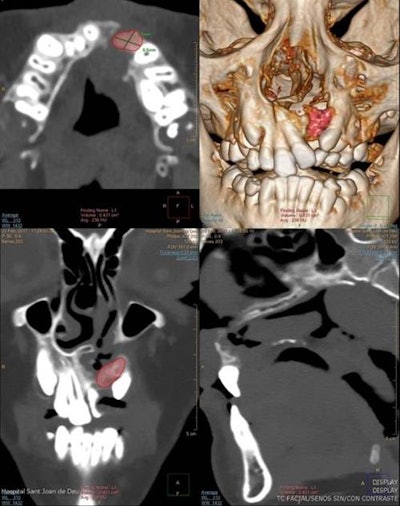

For alveolar bone graft planning, use CT with multiplanar reconstructions (MPR) and surface volumetric (3D), the authors recommended. For planar measurements, axial and coronal CT scans and volumetric measurements before bone grafting give a more accurate picture and help with surgical planning.

"Three-dimensional CT data is especially helpful in evaluating patients with severe craniofacial asymmetry, because they do not suffer from the magnification and distortion-related problems inherent in 2D projections," the authors wrote.

In the four- to six-month follow-up after alveolar bone grafting, the outcome checklist comprises assessment of bone bridge development (osseointegration), measurement of the bone volume of the graft on 3D CT, checking for the presence of oronasal fistula, and evaluation of facial symmetry. Reabsorption of the bone graft occurs mainly during the first postoperative three months and is closely related to long-term outcome, while normal resorption after one year can be up to 30% to 50% of the original graft volume.

When evaluating bone grafts with 3D CT, bone loss is more prominent in the bucco-palatine direction, and if resorption is higher than 50% or there is lack of normal eruption of adjacent teeth, graft failure should be suspected, according to Gómez-Chiari. Facial symmetry can be assessed by measuring the height from the pyriform aperture to the apex of the upper incisor in a coronal plane.